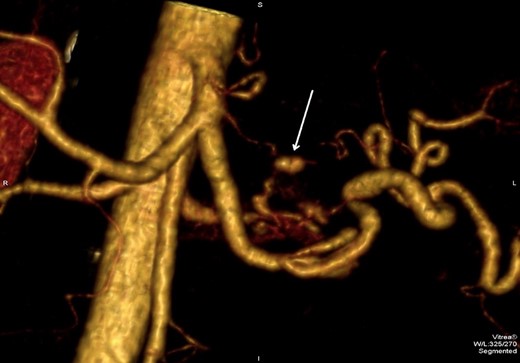

He presented to the local tertiary referral centre complaining of chest pain and the normal ECG, cardiac markers and chest X-ray suggested a non-cardiac cause for the pain. He remained haemodinamically stable and was further investigated with an abdominal ultrasound (USS) and a contrast enhanced computed tomography (CT). The latter demonstrated a 5 × 3.8 cm2 pseudoaneurysm posterior to the stomach and superior to the body of the pancreas but of unclear origin. It also showed a large subcapsular splenic haematoma measuring 10.8 × 7.7 cm2 and a perisplenic collection (Fig. 1).

CT abdomen image shows flow in pseudoaneurysm (arrow) posterior to the stomach and the subcapsular splenic haematoma.